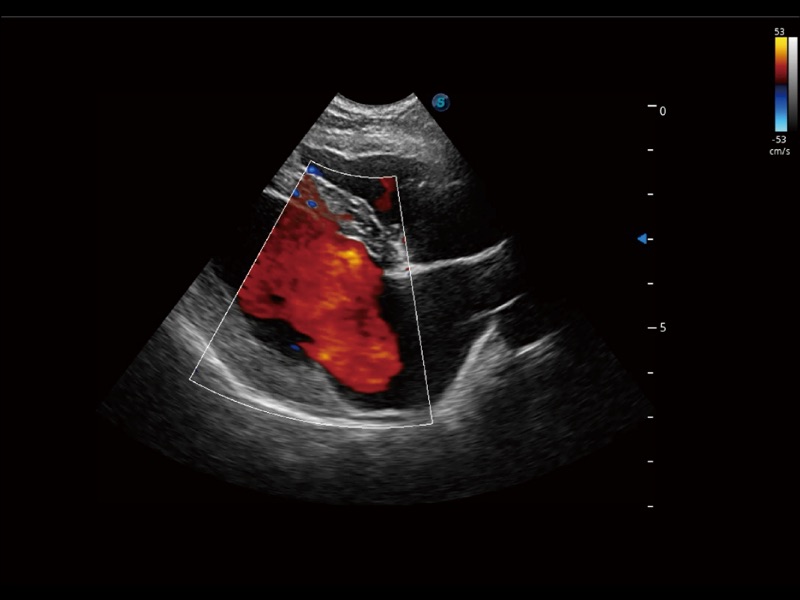

优异的基础图像

(犬)肾脏显微血流

(犬)左室长轴血流

(犬)髂动脉血流

(犬)胎儿主动脉弓立体血流